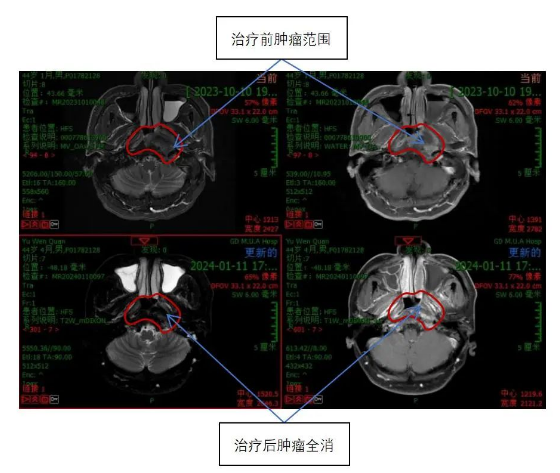

鼻咽癌伴颈部淋巴结、胰头淋巴结及肝转移治疗前后对比